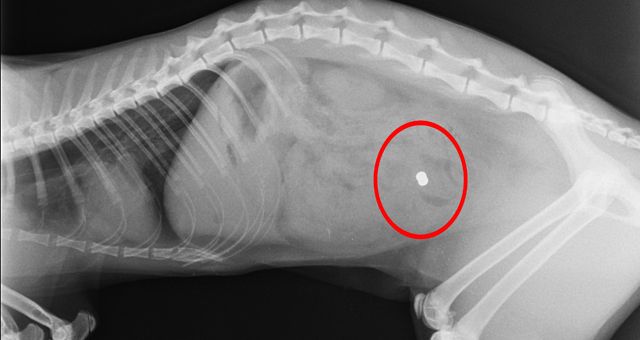

In Kärnten wurde eine Katze mit einem Luftdruckgewehr getötet. Im Mühlviertel konnte das "Diabolo"-Projektil entfernt werden. Die Katzer überlebte.

Bild: Tierklinik Dr. Krebitz/Heute.at-Montage